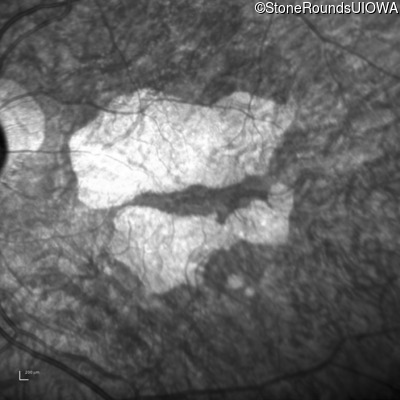

Infrared Fundus Photograph - Right - 10/140

Exemplar